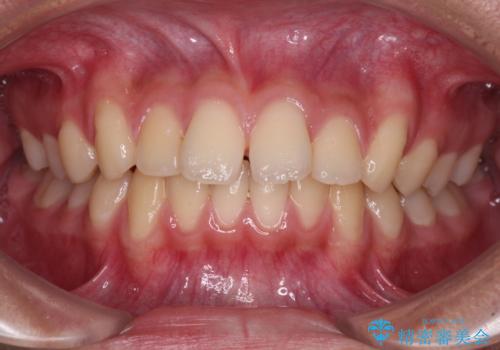

前歯の隙間とデコボコを改善 高校生のインビザライン治療

- 前歯のデコボコと隙間を気にして来院された高校生の患者様です。

下顎前歯が上顎前歯を突き上げるような咬み合わせとなっており、その影響で上顎正中に隙間ができている状態でした。

叢生の程度は軽度であり、本人もしっかりと使用する自信があるとのことだったので、インビザラインによる矯正治療を行うこととしました。

突き上げによる隙間を予防する為に、深い咬み合わせを改善するような治療計画としました。咬み合わせを改善させることはできましたが、隙間は後戻りしやすいので、通常の下顎前歯のみではなく、上顎前歯2本もワイヤーで保定を行いました。